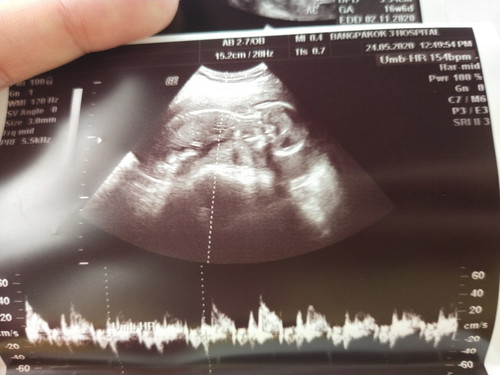

ตอนเห็นลูกในอัตราซาวเป็นครั้งแรกคุณกับแฟนรู้สึกอย่างไร

ตอนเราเห็นเป็นครั้งแรก คุณหมอให้ฟังเสียงหัวใจหันไปเจอแฟนที่เป็นพ่อเด็กอีกที ตาแดงเลย เราก็รู้สึกเหมือนจะร้องเวลาคุณหมอ อธิบายว่านี้เป็นขานี้เป็นแขน หน้าลูกหรือแม้กระทั่งตอนที่หนีบขาไว้นะบางครั้งเราก็หลุดหัวเราะออกมายิ้มทั้งที่ใส่แมส เหมือนโลกมานหยุดว่านี้คือนิ่งมหัศจรรย์ ที่สามารถนอนขดอยู่ในท้องแม่ น่ารักจังอยากเห็นไวๆจังว่าหนูจะน่าตาเป็นแบบไหน นิสัยเหมือนพ่อหรือแม่นะ เข้าใจแม่มากขึ้นเลยค่ะเป็นเหมือนกันไหมค่ะ